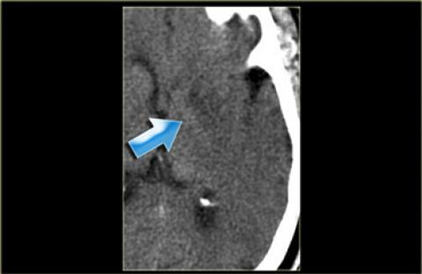

Dấu“dải băng thùy đảo”. Hình ảnh này cần được phân biệt với viêm não do Herpes.